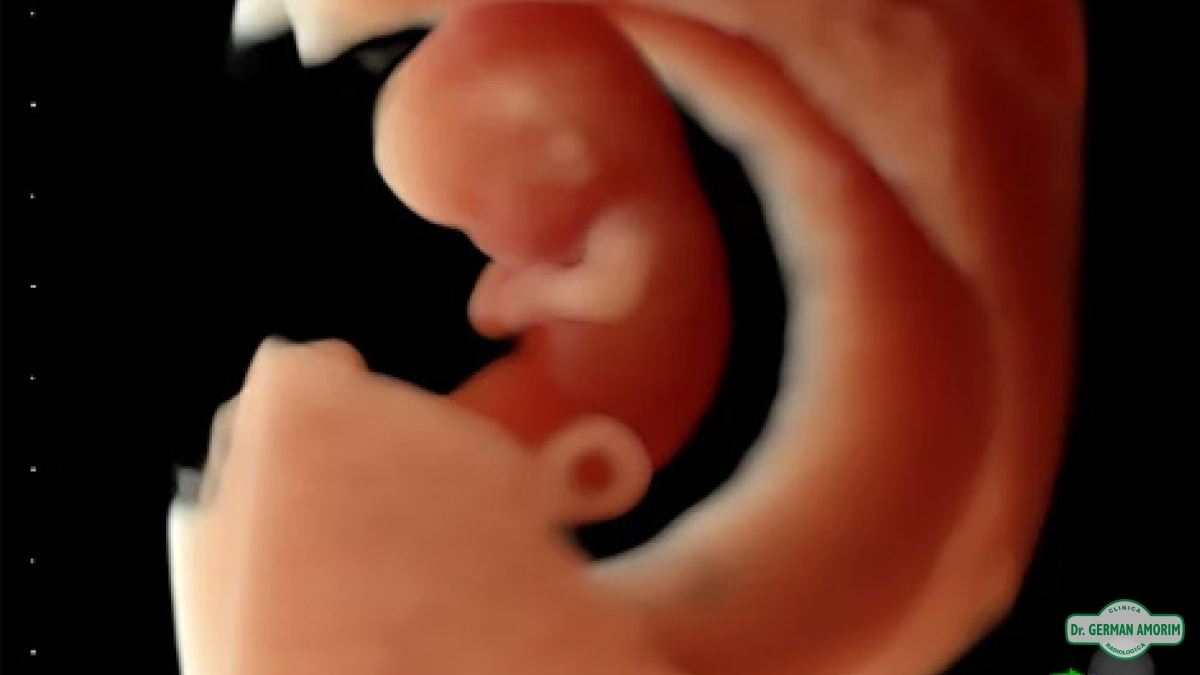

Equipo de Alta Gama Multiproposito para todo tipo de estudios, calidad de imagen superior para el diagnóstico preciso, 4D/5D con HD Live para imágenes del feto únicas color natural, Doppler de.

• Confianza con excelentes imágenes 2D y 3D / 4D, optimizadas para claridad y detalle.